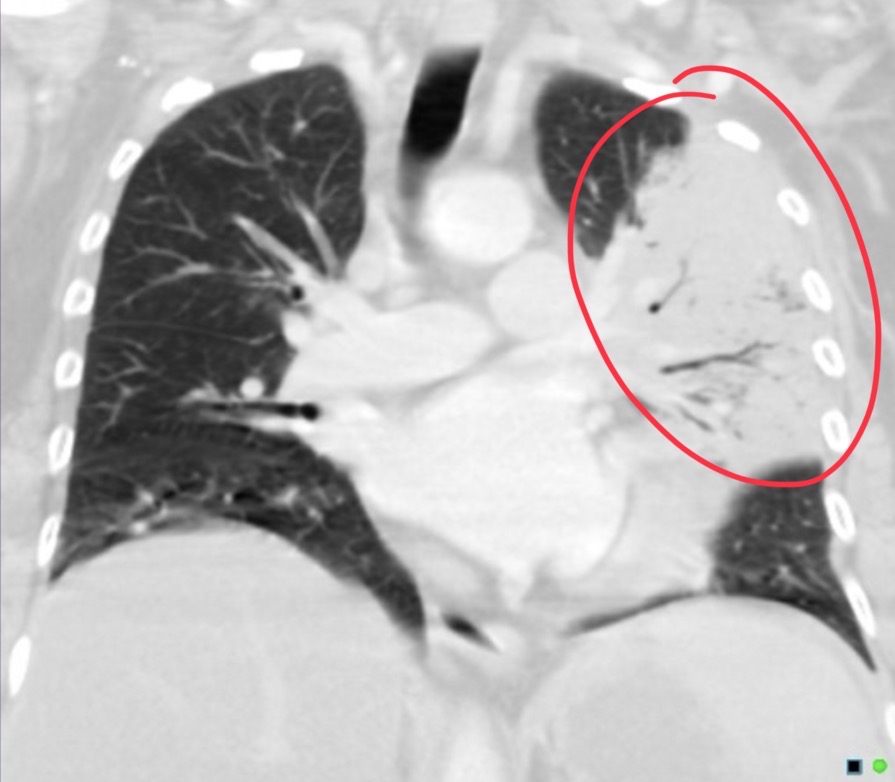

65-year-old female presented with one week history of difficulty passing urine, constipation, and back pain. Patient was found to be in a hyponatremic hyperosmolar and euvolemic state. Serum osmolality is low but urine osmolality is high, urine sodium is high. Pt suspected to have SIADH. no respiratory sx, no smoking hx or fhx of ca.

Non small cell lung carcinoma